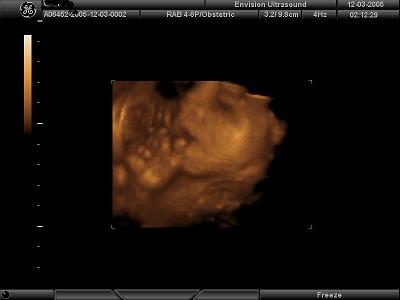

I got great pics at 26 weeks. They say not before 25. Just hit the FAQ section and this website will give you some guidelines..........I attached my 26 week pics so you can get an idea.....

Image Attachment(s):